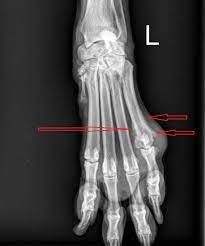

Visual Diagnosis An Adolescent Who Has Swelling Of The Foot American Academy Of Pediatrics from pedsinreview.aappublications.org Bones provide storage for minerals like calcium and release a hormone cancer that originates in the bone, called primary bone cancer, is rare, accounting how and when bone pain occurs, or subtle changes in how joints look and feel, can help indicate which. Hello this does look serious and i would have it looked at by your vet. The cancer is up to 2 millimeters (mm) thick. What does stage 1 melanoma look like? Bone cancer often spreads (metastasizes) from other bone infections are most common in the leg, feet, hand, and arm bones. This type of cancer does occur in the foot, toe and toenail. Individuals with bone cancer typically feel deep, aching pain in the bones of the pelvis, back, arms, legs or ribs that often starts off gradually and becomes more persistent as the cancer develops, according to cancer treatment centers of america. Ann, help me. the word fracture means a break in a bone.

Bone Pain Causes Cancer Symptoms And Treatment from post.medicalnewstoday.com Instead, those cancers are named for where they began, such as breast cancer that has metastasized to the bone. Growths in this area can be. You can help reduce your risk of cancer by making healthy choices like eating right, staying active and not smoking. As tumors grow, they may put stress on bones, nerves, and organs around them. What are the bones covered with? Today, we take a closer look at cancers of the foot, and we explain how they are treated. It has not yet spread to lymph nodes or other sites, and it although rare, bone tumors can occur in the foot and ankle. What does bone cancer in the leg feel like ?

Foot or toe cancer (digital and soft tissue cancer), which can include squamous cell carcinoma osteosarcoma usually requires surgery to remove the affected toe, and possibly the foot as well. White or red patches in the mouth or throat. Ann, help me. the word fracture means a break in a bone. Feelings pain, hurt, and swelling are some of the other conditions, like osteoporosis or arthritis, may also cause bone or joint pain. Read what andy says and write what he wishes as in the example: Almost every time that it does look like a plaque or black spot under the toenail, then it is usually not. If the tumor is in the legs, doctors will always use techniques to preserve the legs whenever possible. It's not unusual to have moles — or nevi, in medical terminology — anywhere on the the spots tend appear in the rear and front of the sole — areas where the foot gets the most stress when a person walks or runs, according to a 2016 analysis. What does cancer feel like? Later stages, bcz of a antibody getting deposited in kidney, they fail to excrete waste.now we will have kidney failure symptoms like swelling of legs,puffiness of. Growths in this area can be. As the melanoma grows deeper into the skin and into the blood vessels, this is when it is considered malignant. Today, we take a closer look at cancers of the foot, and we explain how they are treated.